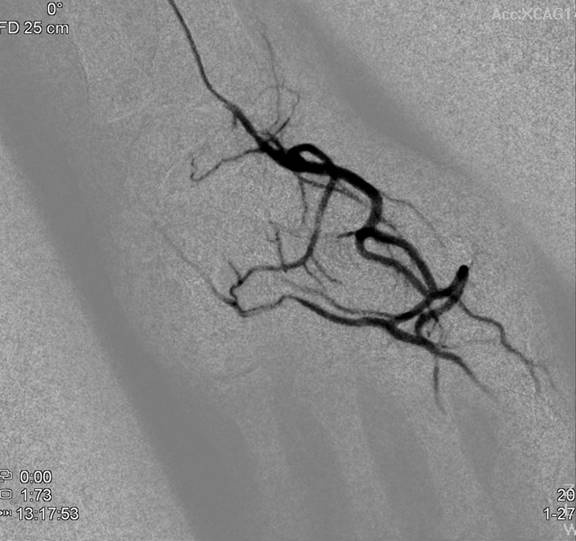

圖說二:因職業傷害無法工作的廚師,經員榮醫院心臟內科主任林彤宥醫師在X光透視下導引微導管,將栓塞劑注入異常增生血管,目前已快樂地在澳洲工作。